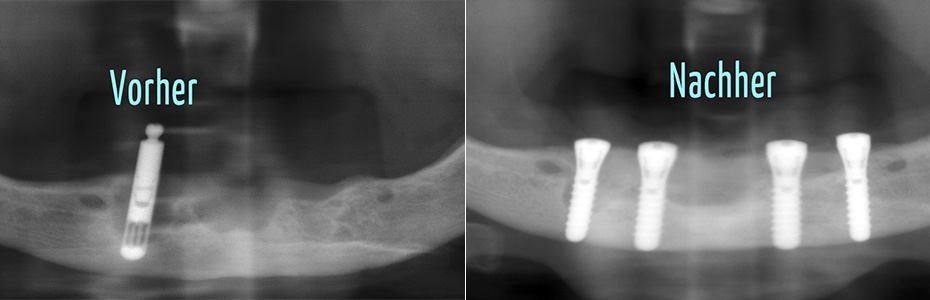

Implantologische Misserfolge

Ein Misserfolg muss nicht immer ein Implantatverlust sein. Auch eine Abweichung von dem mit dem Patienten geplanten und dem erzielbaren Ergebnis kann als Misserfolg verstanden werden.

Vom Misserfolg zur erfolgreichen Behandlung

Unkenntnis oder Versäumnisse

Implantologische Misserfolge können auf Unkenntnis von Begleitumständen und einer ungünstigen Abfolge von Ereignissen oder Versäumnissen beruhen.

Wir zeigen Ihnen an dieser Stelle Patientenfälle, die vorbehandelt in die Praxisklinik für dentale Implantologie gekommen sind und für die wir im Rahmen einer Weiterbehandlung eine Lösung gefunden haben. In vielen Fällen haben wir festgestellt, dass die Misserfolge vorhersehbar und vermeidbar gewesen wären.